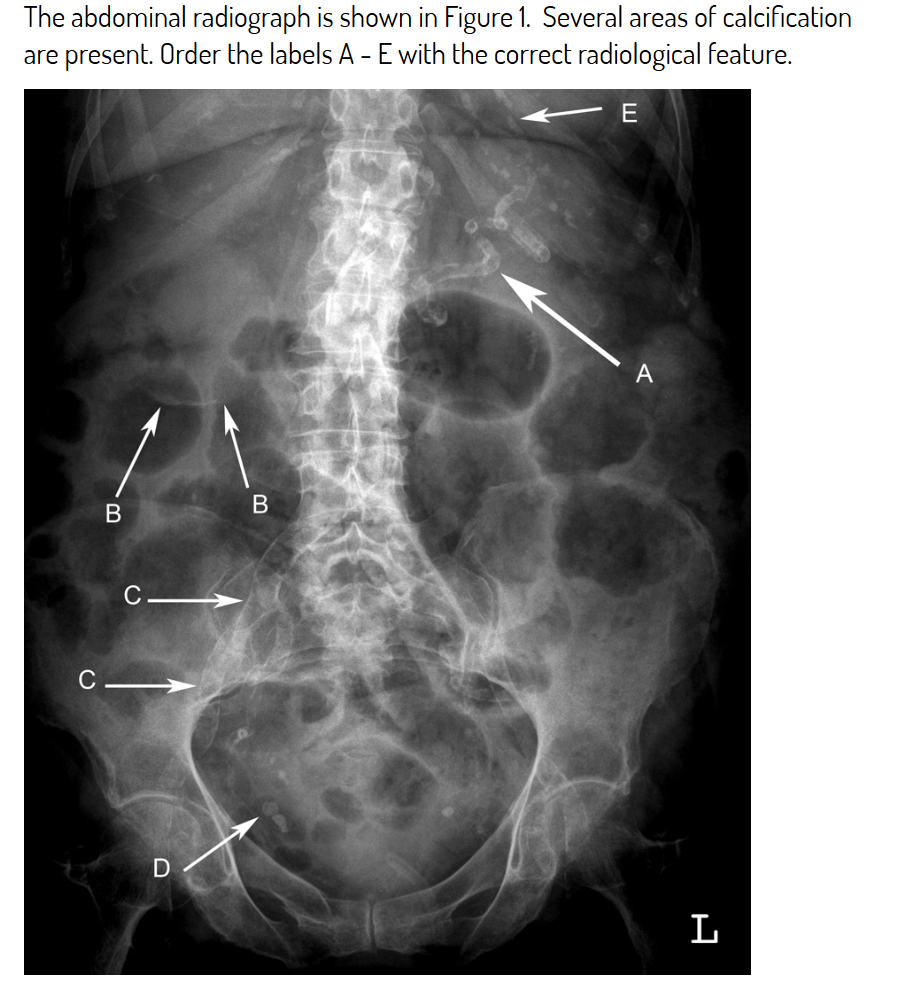

A - splenic artery calcification

B - gallbladder wall calcification

C- right iliac artery calcification

D - phlebolith

E - costal cartilage calcification